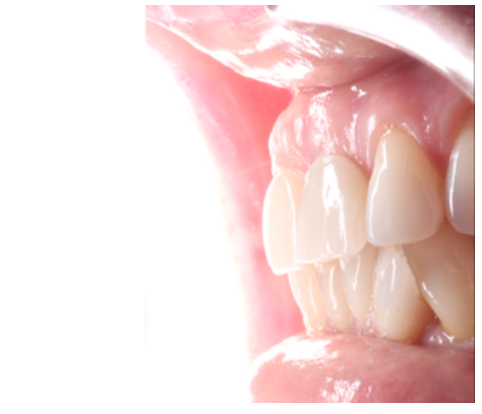

Clinical case: A 32-year-old female patient who attended for a possible root fracture of the upper left central incisor (ULCI), accompanied by a periodontal abscess at the bottom of the vestibule of the same tooth. A clinical and radiological examination established that the prognosis of the ULCI was unfavourable for conservative treatment. After evaluating the clinical features of the case, the treatment plan to extract the ULCI followed immediately by an osseointegrated implant (OII) and loading of a provisional prosthesis on the implant.

Conclusions: Rehabilitation on implants in situations of tooth loss in the aesthetic anterior sector, especially in young patients, requires a multidisciplinary treatment plan to extract the tooth and insert an OII in the correct 3-dimensional position. Various aspects need to be taken into account for this, particularly the residual remaining bone, the position of the gingival margin and preservation and conditioning of the peri-implant hard and soft tissues by means of grafts and proper handling of provisional prosthesis, until an ideal emergence profile and gingival contour is achieved before the final crown.

The benefits of immediate loading include a marked reduction in surgical interventions, less temporary dilation of the treatment and even better psychological and social wellbeing for the patient. In cases with a significant aesthetic requirement, immediate loading or provisionalisation, and post-extraction placement of the OII minimise alterations due to tooth loss and maintain the emergence profile, soft tissue contour and gingival papillae5-7.

Different protocols have also been established for the management of the anterosuperior aesthetic sector, in addition to performing the immediate implant and provisional crown, including placing material between the OII and the buccal cortical to minimise possible collapse and the management of peri-implant soft tissue8-11.